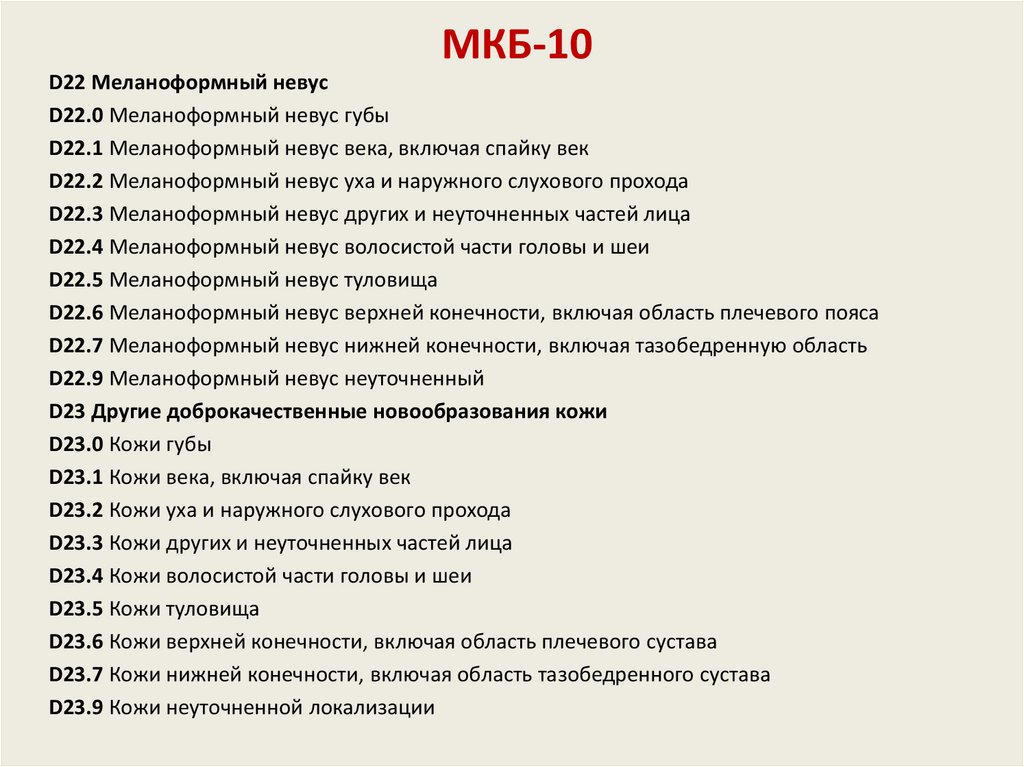

Код мкб 10 атерома головы

Код мкб 10 атерома головы 109 фото